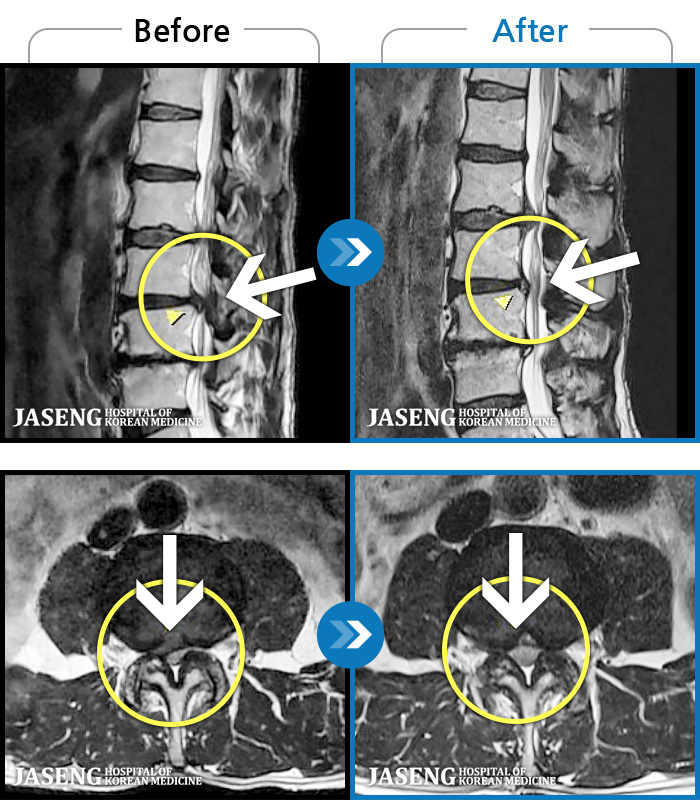

1,237 MRI ũ ʸ Ȯϼ.

MRI ġ

㸮 ϻ .